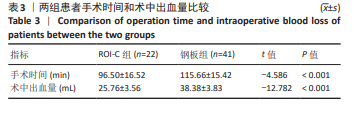

2.7 术后并发症评估 2.7.1 吞咽困难情况分析 在ROI-C组中,术后出现吞咽困难的病患数为4例,占该组总数的18%(4/22),此症状在术后3个月内自行缓解。相比之下,钢板组术后发生吞咽困难的患者较多,共计14例,发生率为34%(14/41);术后3个月时,钢板组内仍有7例(17%)患者持续存在吞咽困难;至术后6个月的随访时,这些患者的吞咽困难症状均得到显著改善或消失。统计结果显示,两组间在术后吞咽困难的发生率上未见显著性差异(χ2=1.788,P=0.181);ROI-C组术后3个月吞咽困难发生率显著低于钢板组(Fisher确切概率法P=0.041)。 2.7.2 邻近节段退变情况分析 ROI-C组与钢板组患者在术后3,6个月的时间点上,均未报告有邻近节段退变发生。术后12个月,ROI-C组中观察到邻近节段退变病例1例,占比5%(1/22);而钢板组内则出现3例邻近节段退变,占比7%(3/41),两组差异无显著性意义(χ2=0.029,P=0.866)。 两组术后12个月的上邻近节段和下邻近节段椎间隙高度均较术后即刻明显降低,但钢板组邻近椎间隙高度下降程度较ROI-C组明显增高,差异有显著性意义(P < 0.05)。两组间术前、术后即刻、术后3,6,12个月的C2-7 Cobb角、T1倾斜角、椎间隙高度相比差异均无显著性意义(P > 0.05)。 2.8 植入物与宿主的生物相容性 术后6个月时,ROI-C组出现1例未融合(5%),钢板组出现1例(2%);术后12个月时两组患者全部获得融合,两组间无明显差异(P < 0.05)。两组术后均未出现植入物周围感染、过敏反应、免疫反应及排斥反应。部分患者(ROI-C组3例、钢板组9例)术后出现体温轻度升高(小于38 ℃),在术后3 d内均得到恢复。术后各时间节点均未发现植入物破损、松动、脱落。 2.9 典型病例 影像学资料见图3,4。"